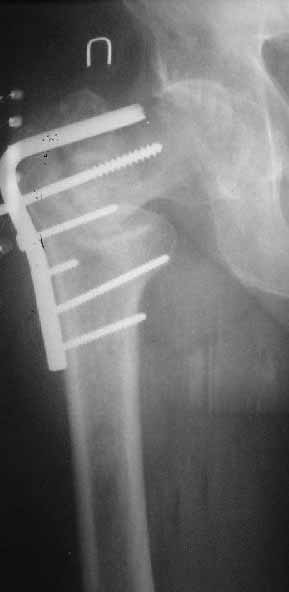

Закрытый интрамедуллярный остеосинтез или он же в сочетании с чрескожной межвертельной остеотомией в случае внесуставного несращения - это, по сути, эндопротезирование с собственной шейкой и головкой бедра. Но через 3-4 разреза по 1,5-2 см. Нога сразу опорная, сустав конгруэнтный - чего еще надо? В приложении - похожее несращение тоже у пациента за 60 и с диабетом 2 типа...

Фиксировать после остеотомии можно и клинковой пластиной, и DHS - это традиционная техника, хорошо описанная в книжках. Проксимальным бедренным гвоздем привлекательнее тем, что можно остеотомию делать с открытым клином.

Важно достигнуть хорошую ротационную стабильность фиксации. Угловая V-образная пластинка стабильнее , а еще лучше два винта. Проксимальный бедренный гвоздь с двумя винтами - PFN, Syntes или любой похожий по моим понятиям лучший вариант.